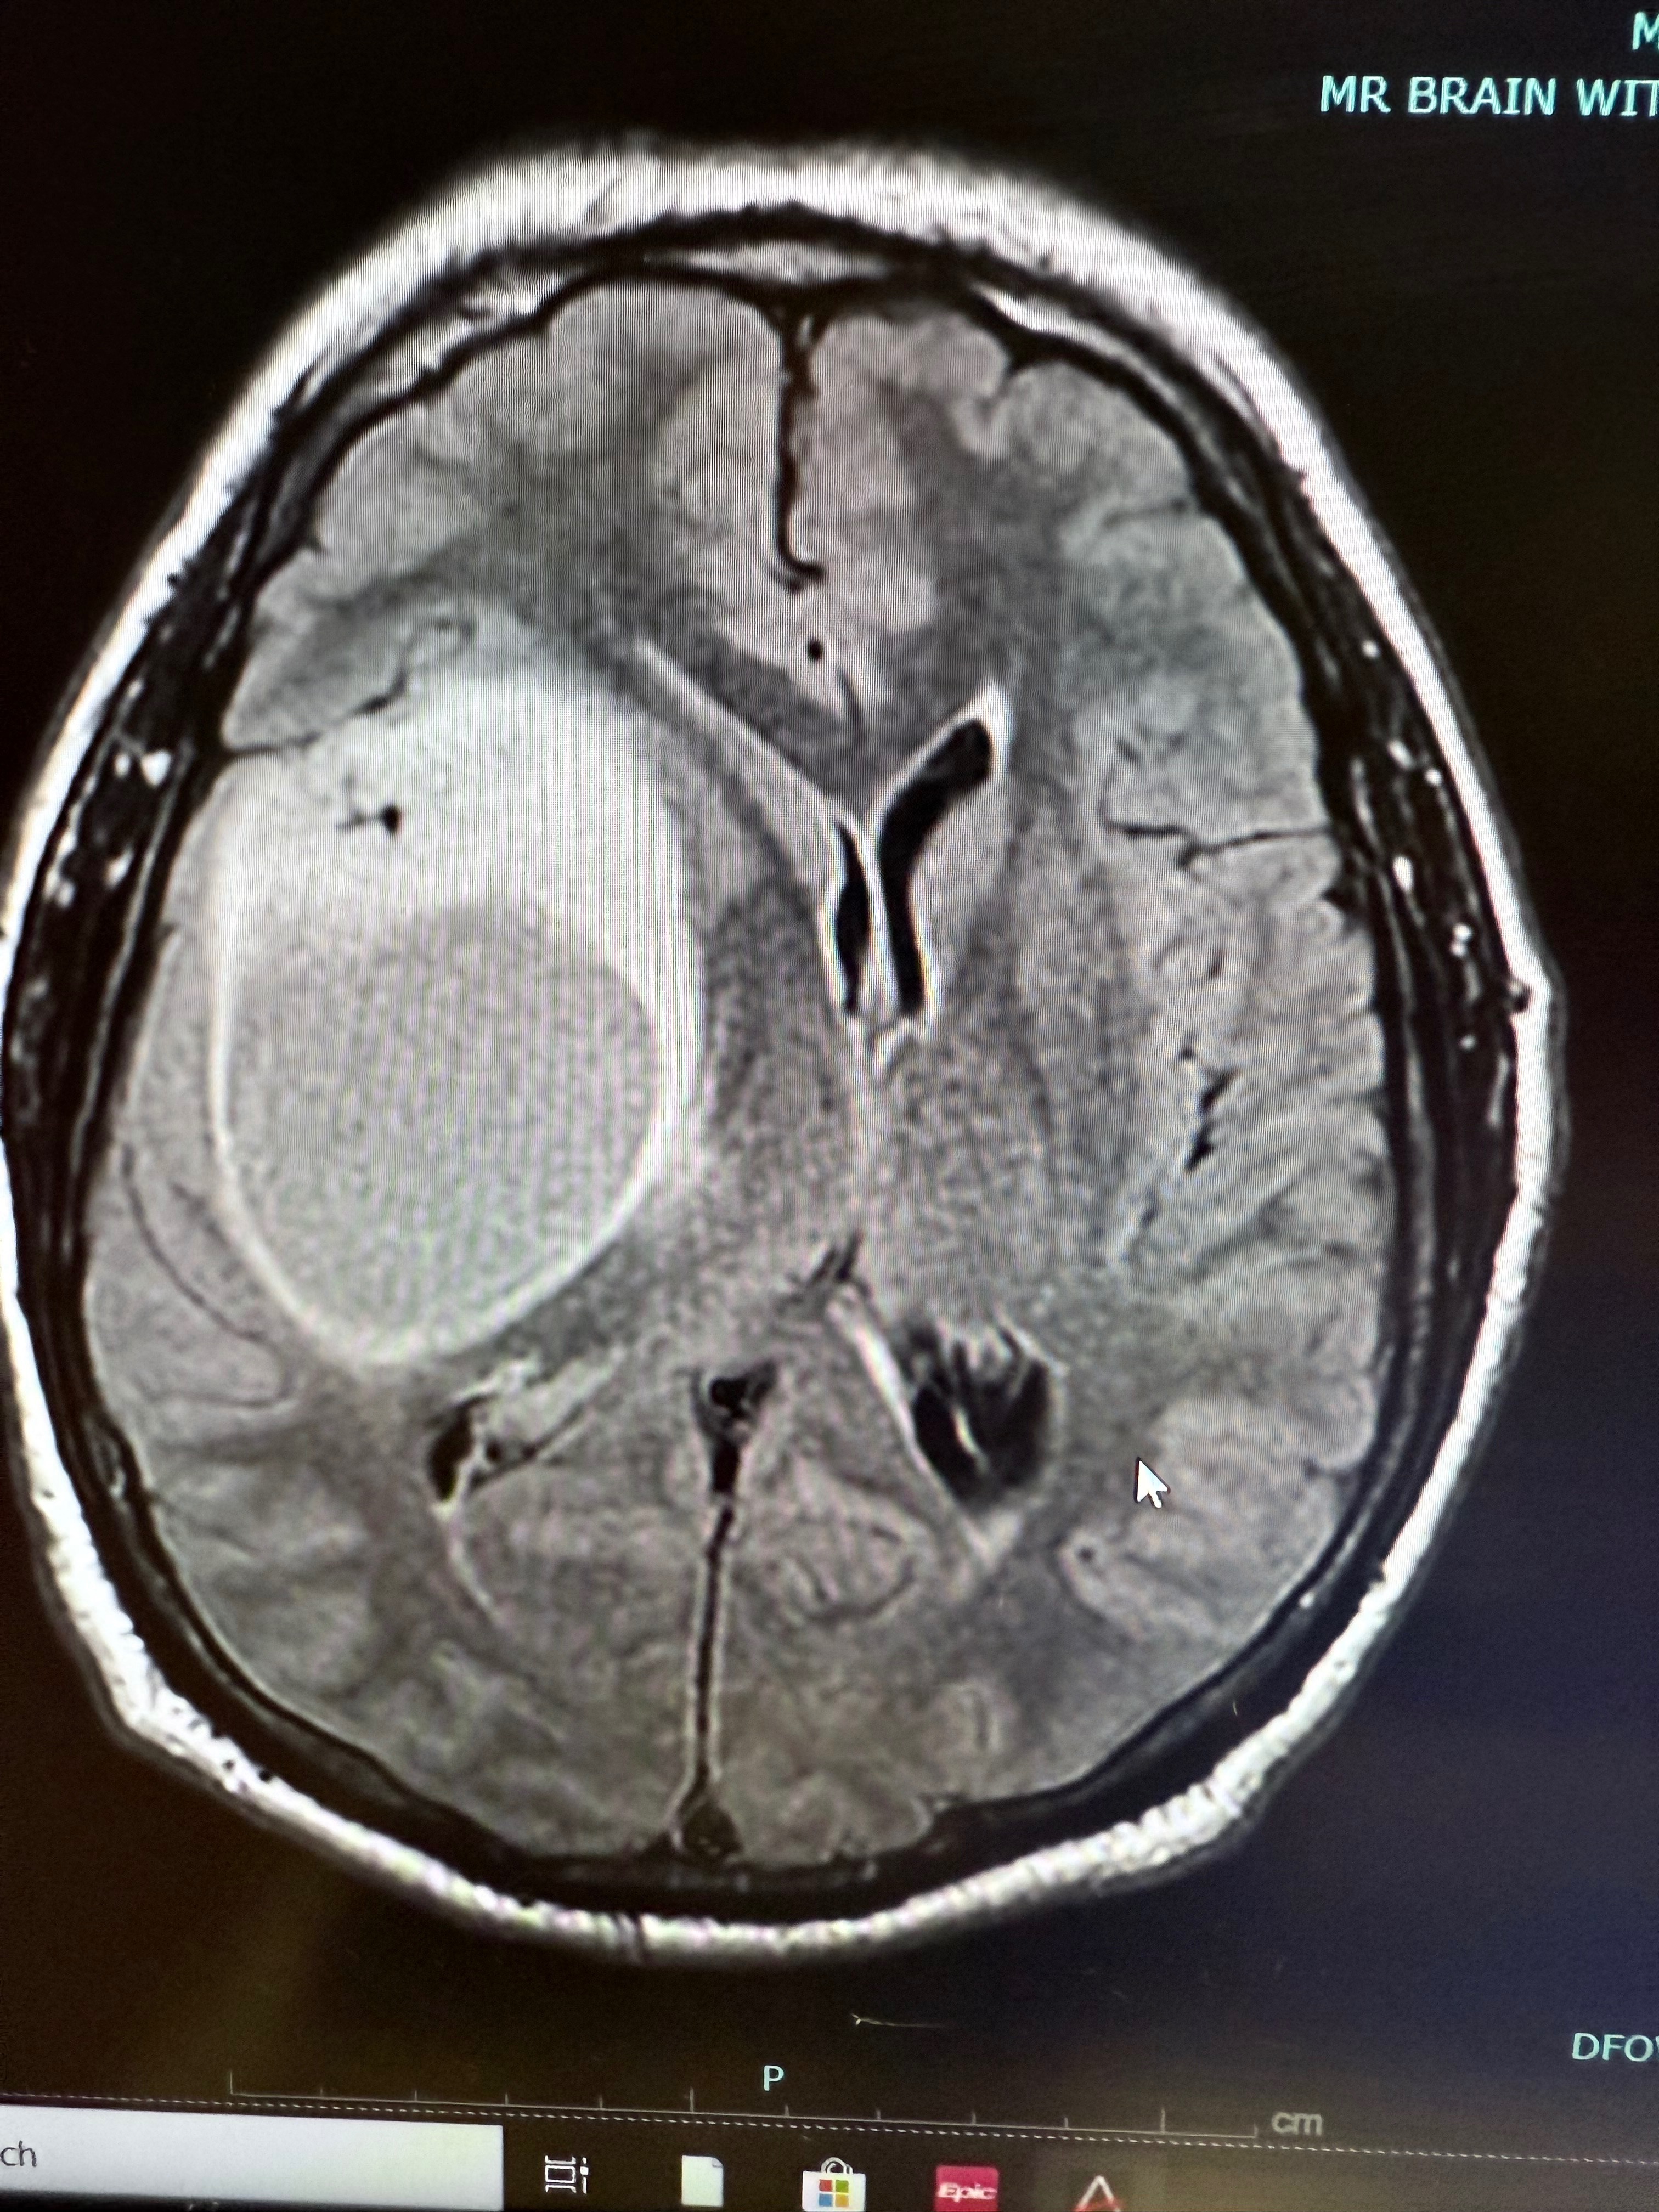

On November 21st, we started going through the craziest thing we thought we would ever go through. Starting with an emergency “flight for life” to Colorado Springs for a fist-sized brain tumor that we discovered in Craig’s head.

Between these 3 surgeries, we lived at the hospital for almost a month. We left the hospital with an incurable and aggressive grade 4 Brain Cancer diagnosis.